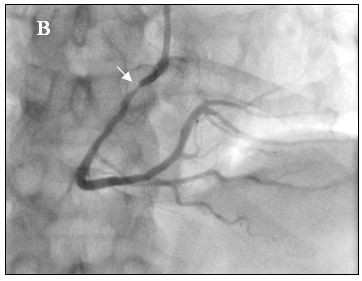

Tại phòng thông tim huyết áp bệnh nhân thấp 80/60mmHg nên chúng tôi không dùng Nitroglycerin. Sau khi chụp thấy hẹp nặng lan tỏa ở cả ba nhánh của động mạch vành, không loại trừ do co thắt nên chúng tôi đã tiến hành bơm 500µg Nitroglycerin vào động mạch vành. Kết quả chụp lại hiện tượng trên hoàn toàn biến mất, động mạch vành phải và trái thâm nhiễm nhẹ nhưng đều có kích thước lớn hơn nhiều so với ban đầu, dòng chảy TIMI 3 (hình 3a-3b), đồng thời huyết áp của bệnh nhân cũng cải thiện rõ 120/80 mmHg.

Hình 3a: Nhánh LCX, OM và LAD sau khi bơm Nitroglycerin

Hình 3b: Nhánh RCA sau khi bơm Nitroglycerin.